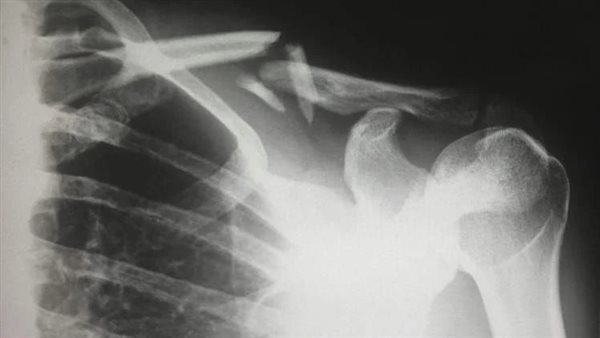

ووفقًا لتقرير صادر عن مستشفى شيندو للطب التقليدي في مدينة تشنغدو، فإن الفحوصات أظهرت تراجعًا ملحوظًا في كثافة العظام لدى السيدة، ما جعل عظامها هشة إلى درجة أنها تعرضت للكسر من حركة بسيطة. وأفاد الدكتور لونغ شوانغ، المشرف على حالتها، أن المريضة اعتادت على تغطية بشرتها بشكل دائم وحرصت على استخدام واقي الشمس في جميع تنقلاتها، ما حرم جسدها من المصدر الأساسي لإنتاج فيتامين د.